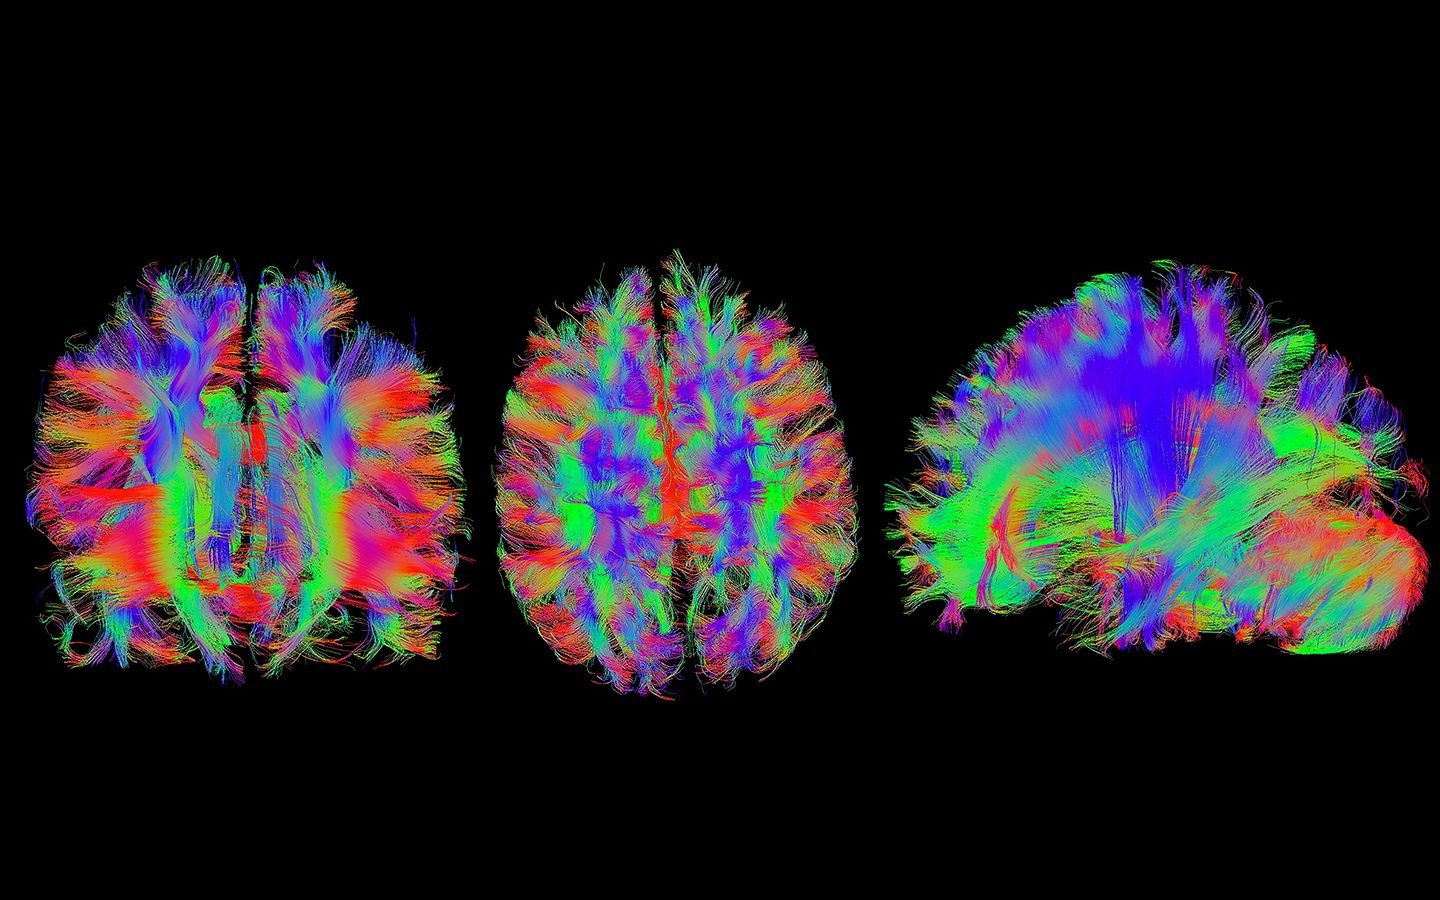

Evaluación integral con RM multimodal: perfusión, difusión, tensor e imágenes de susceptibilidad para ACV isquémico y hemorrágico.

RM 1.5T con secuencias neuro especializadas

Espectroscopia, volumetría de hipocampos, perfusión dinámica y fMRI para evaluación completa de función y patología cerebral.